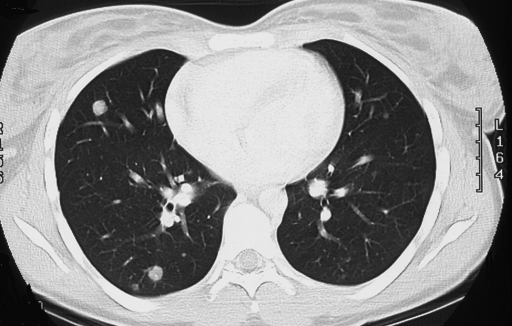

Метастазы в легких на КТ

Гематогенные метастатические узлы в легких на КТ имеют довольно четко очерченные и ровные контуры. Нечеткие, расплывчатые или лучистые контуры наблюдаются в том случае, если есть инвазивный рост в окружающую легочную ткань. Локализуются преимущественно в нижних, периферических отделах легких, хаотично, без очевидной связи с бронхами и крупными легочными сосудами.

Метастазы чаще всего представлены узловыми образованиями в легочной ткани вне строгой связи с легочными артериями или венами. Для них характерны следующие КТ-признаки:

Вторичные узлы гематогенного характера чаще всего имеют ровные края, четкие контуры и однородную структуру. Возможны изменения структуры опухоли вследствие кровоизлияния в паренхиму, обызвествлений, некроза центральной части узла, а также рубцов. Края узла могут стать нечеткими, расплывчатыми, если опухоль провоцирует отек легочной паренхимы, либо «лучистыми», если имеет место опухолевый лимфангиит.

Множественные гематогенные вторичные узлы при раке почки, компьютерная томография (КТ).